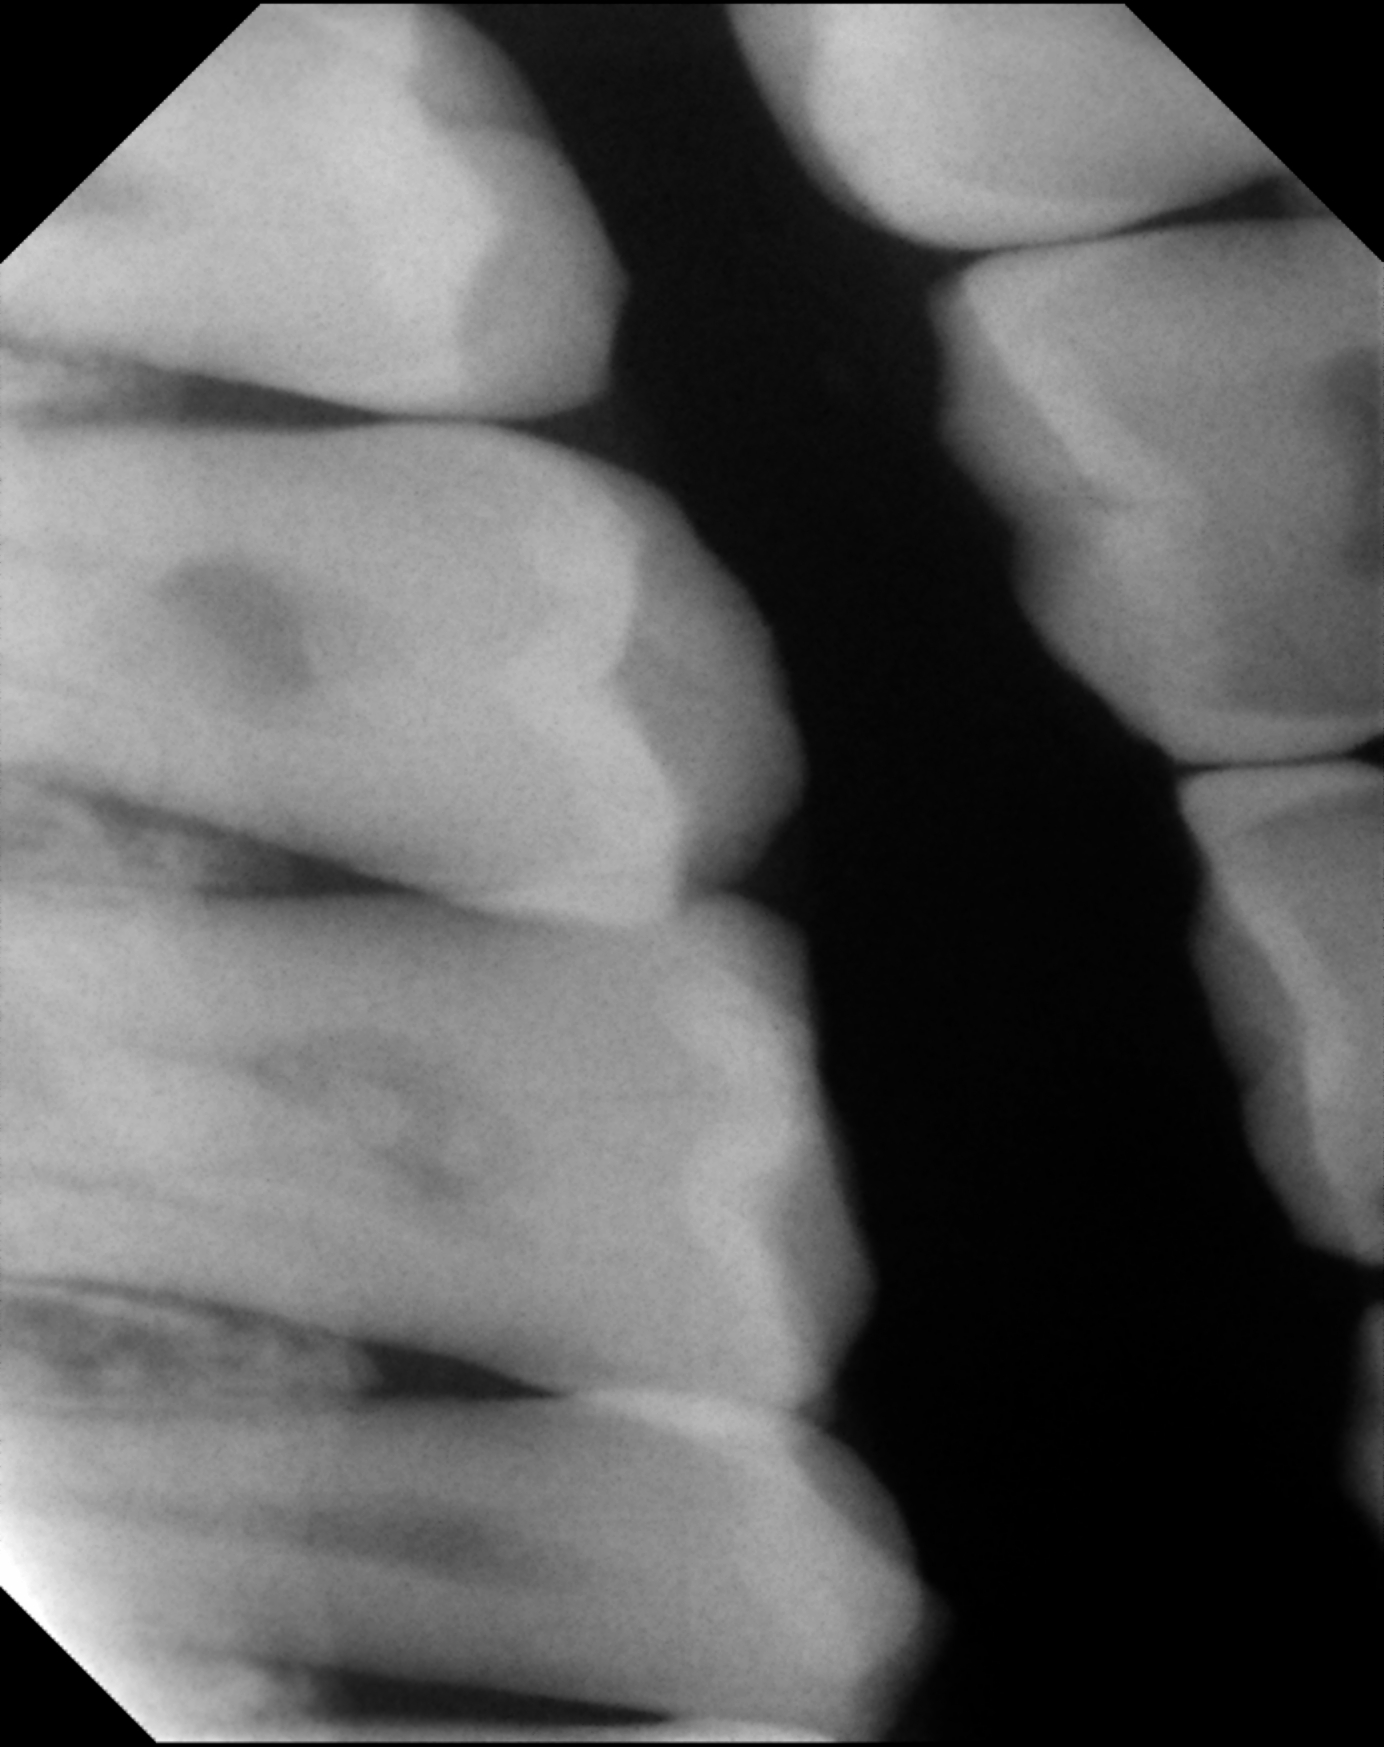

Gendex Sensor

QuickRay Sensor Image